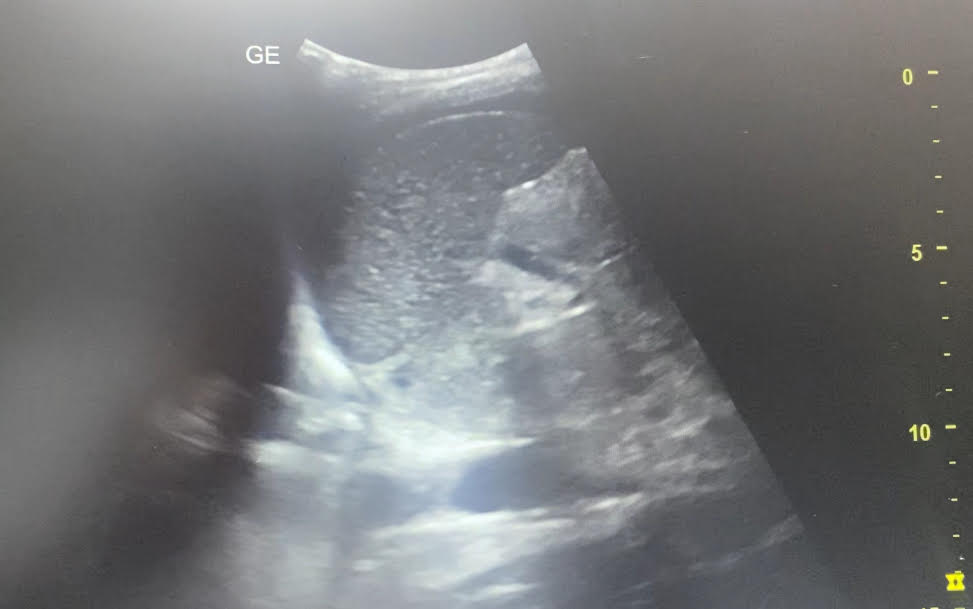

Vemos contenido anecogénico poco limpio bajo cúpulas diafragmáticas sobre todo en ambos flancos. Hígado con vasos portales muy birrefringentes. Riñón izquierdo algo desestructurado pero con difícil ventana.

La paciente ingresa en observación para tratamiento analgésico y preparación para cirugía urgente. En la analítica no presentaba leucocitosis pero sí reactantes de fase aguda elevados. Previa a la cirugía se realiza TAC abdominal con objeto de localizar la posible perforación que aparecía en antro gástrico y en la cirugía se objetiva el líquido ascítico purulento compatible con las imágenes captadas en ecografía.